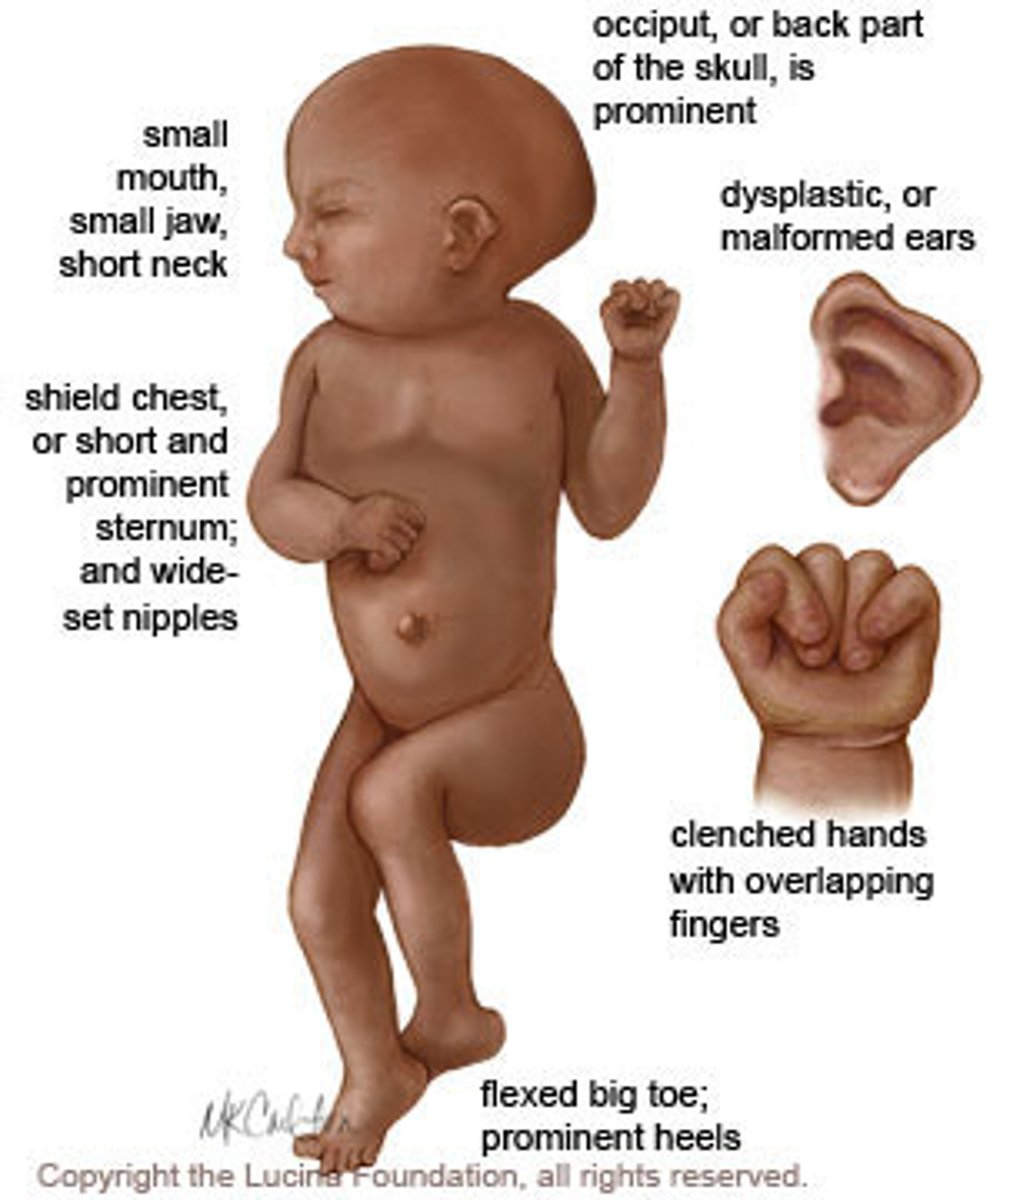

Which trisomy is associated with rocker bottom feet & clenched hands with overlapping fingers?

trisomy 18 (edwards)

high infant mortality :(